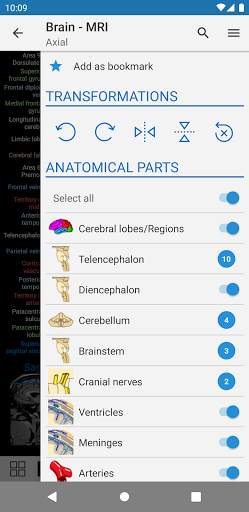

- Pilih label anatomi berdasarkan kategori

- Anda sekarang dapat menyembunyikan struktur satu per satu (tombol baru di dalam tampilan deskripsi) dan menampilkannya lagi di menu sebelah kanan